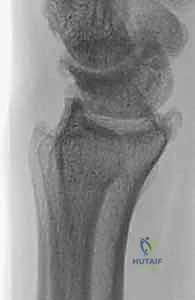

- التصوير بالأشعة السينية (X-rays): هي الخطوة الأولى والأساسية. تظهر الأشعة بوضوح تآكل الغضروف، تضيق المسافة المفصلية، وتكوّن الزوائد العظمية (المنقار العظمي).

| الأشعة السينية | مسافة مفصلية واضحة، عظام ناعمة | تضيق المسافة المفصلية، تكون نتوءات عظمية (Osteophytes)، وتصلب العظم تحت الغضروف |